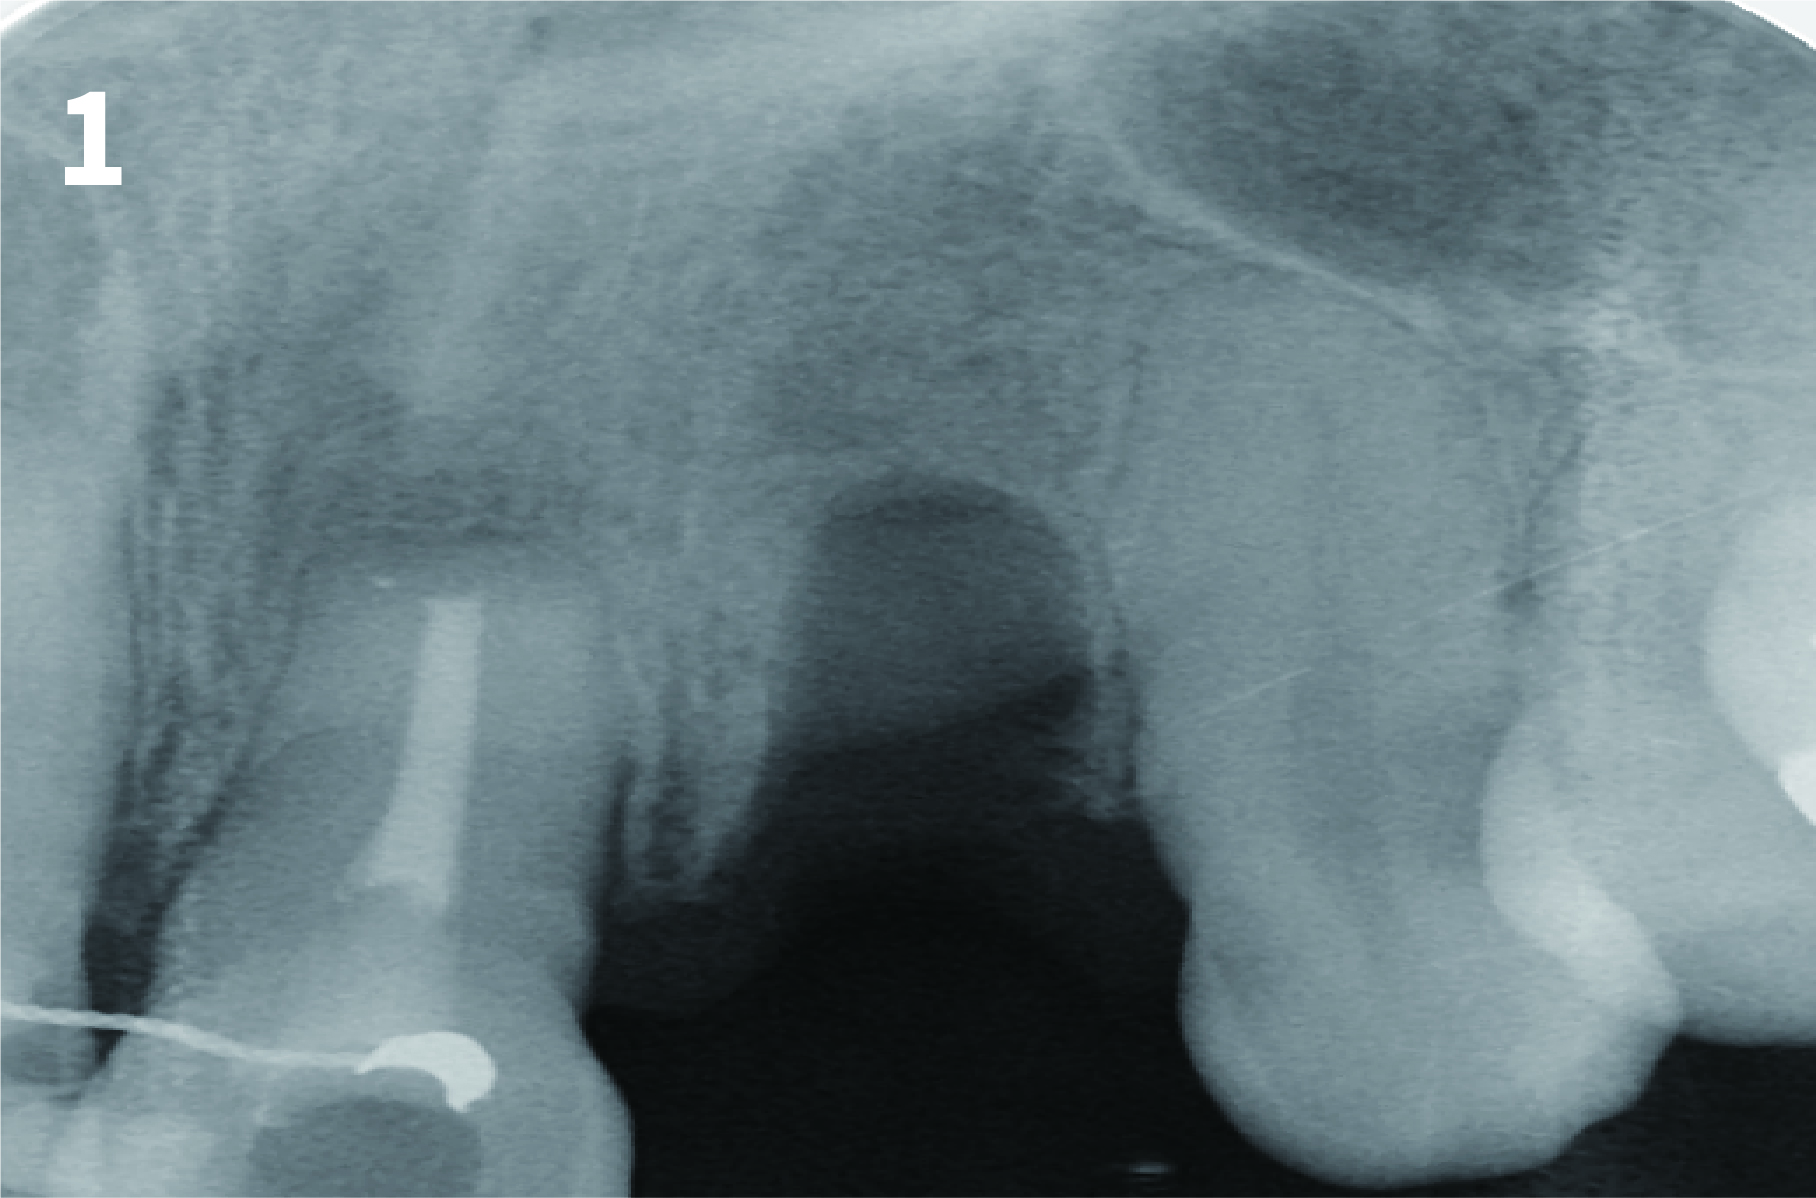

Case 1: Simply Augmented Severe Dehiscence Defect on Anterior Area